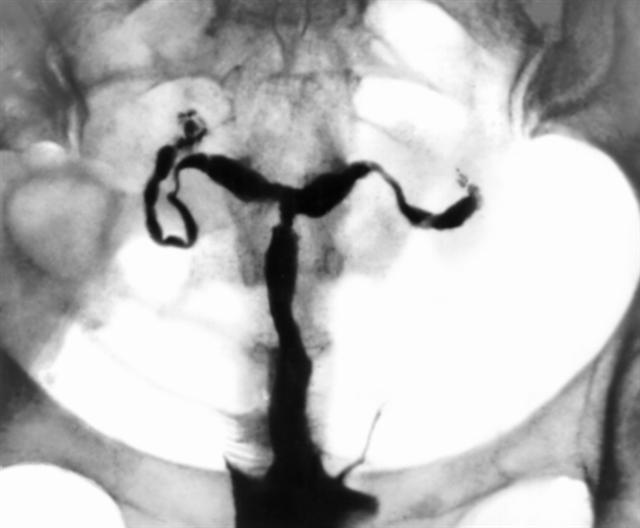

Рис. 16. Гистеросальпингограмма при туберкулезном сальпингите и эндометрите: полость матки деформирована (имеет форму трилистника), маточные трубы ригидны, в их дистальных отделах видны негомогенные тени («ватные тампоны»).